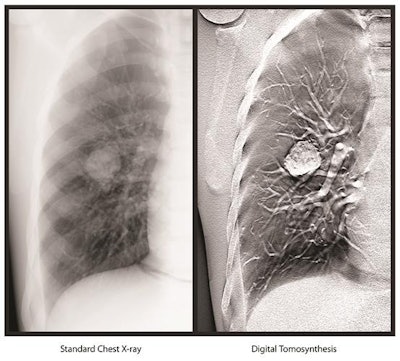

Carestream Health has garnered U.S. Food and Drug Administration (FDA) 510(k) clearance for its digital tomosynthesis (DT) software, adding a 3D capability to the firm's general radiography technology.

The tomosynthesis technology employs a single sweep of x-ray exposures and streamlines operator workflow by separating DT exposure acquisition from image volume formation, according to the vendor. This enables data to be generated from a series of low-dose x-ray images of an organ that were acquired at the same x-ray exposure but from different angles, Carestream said.